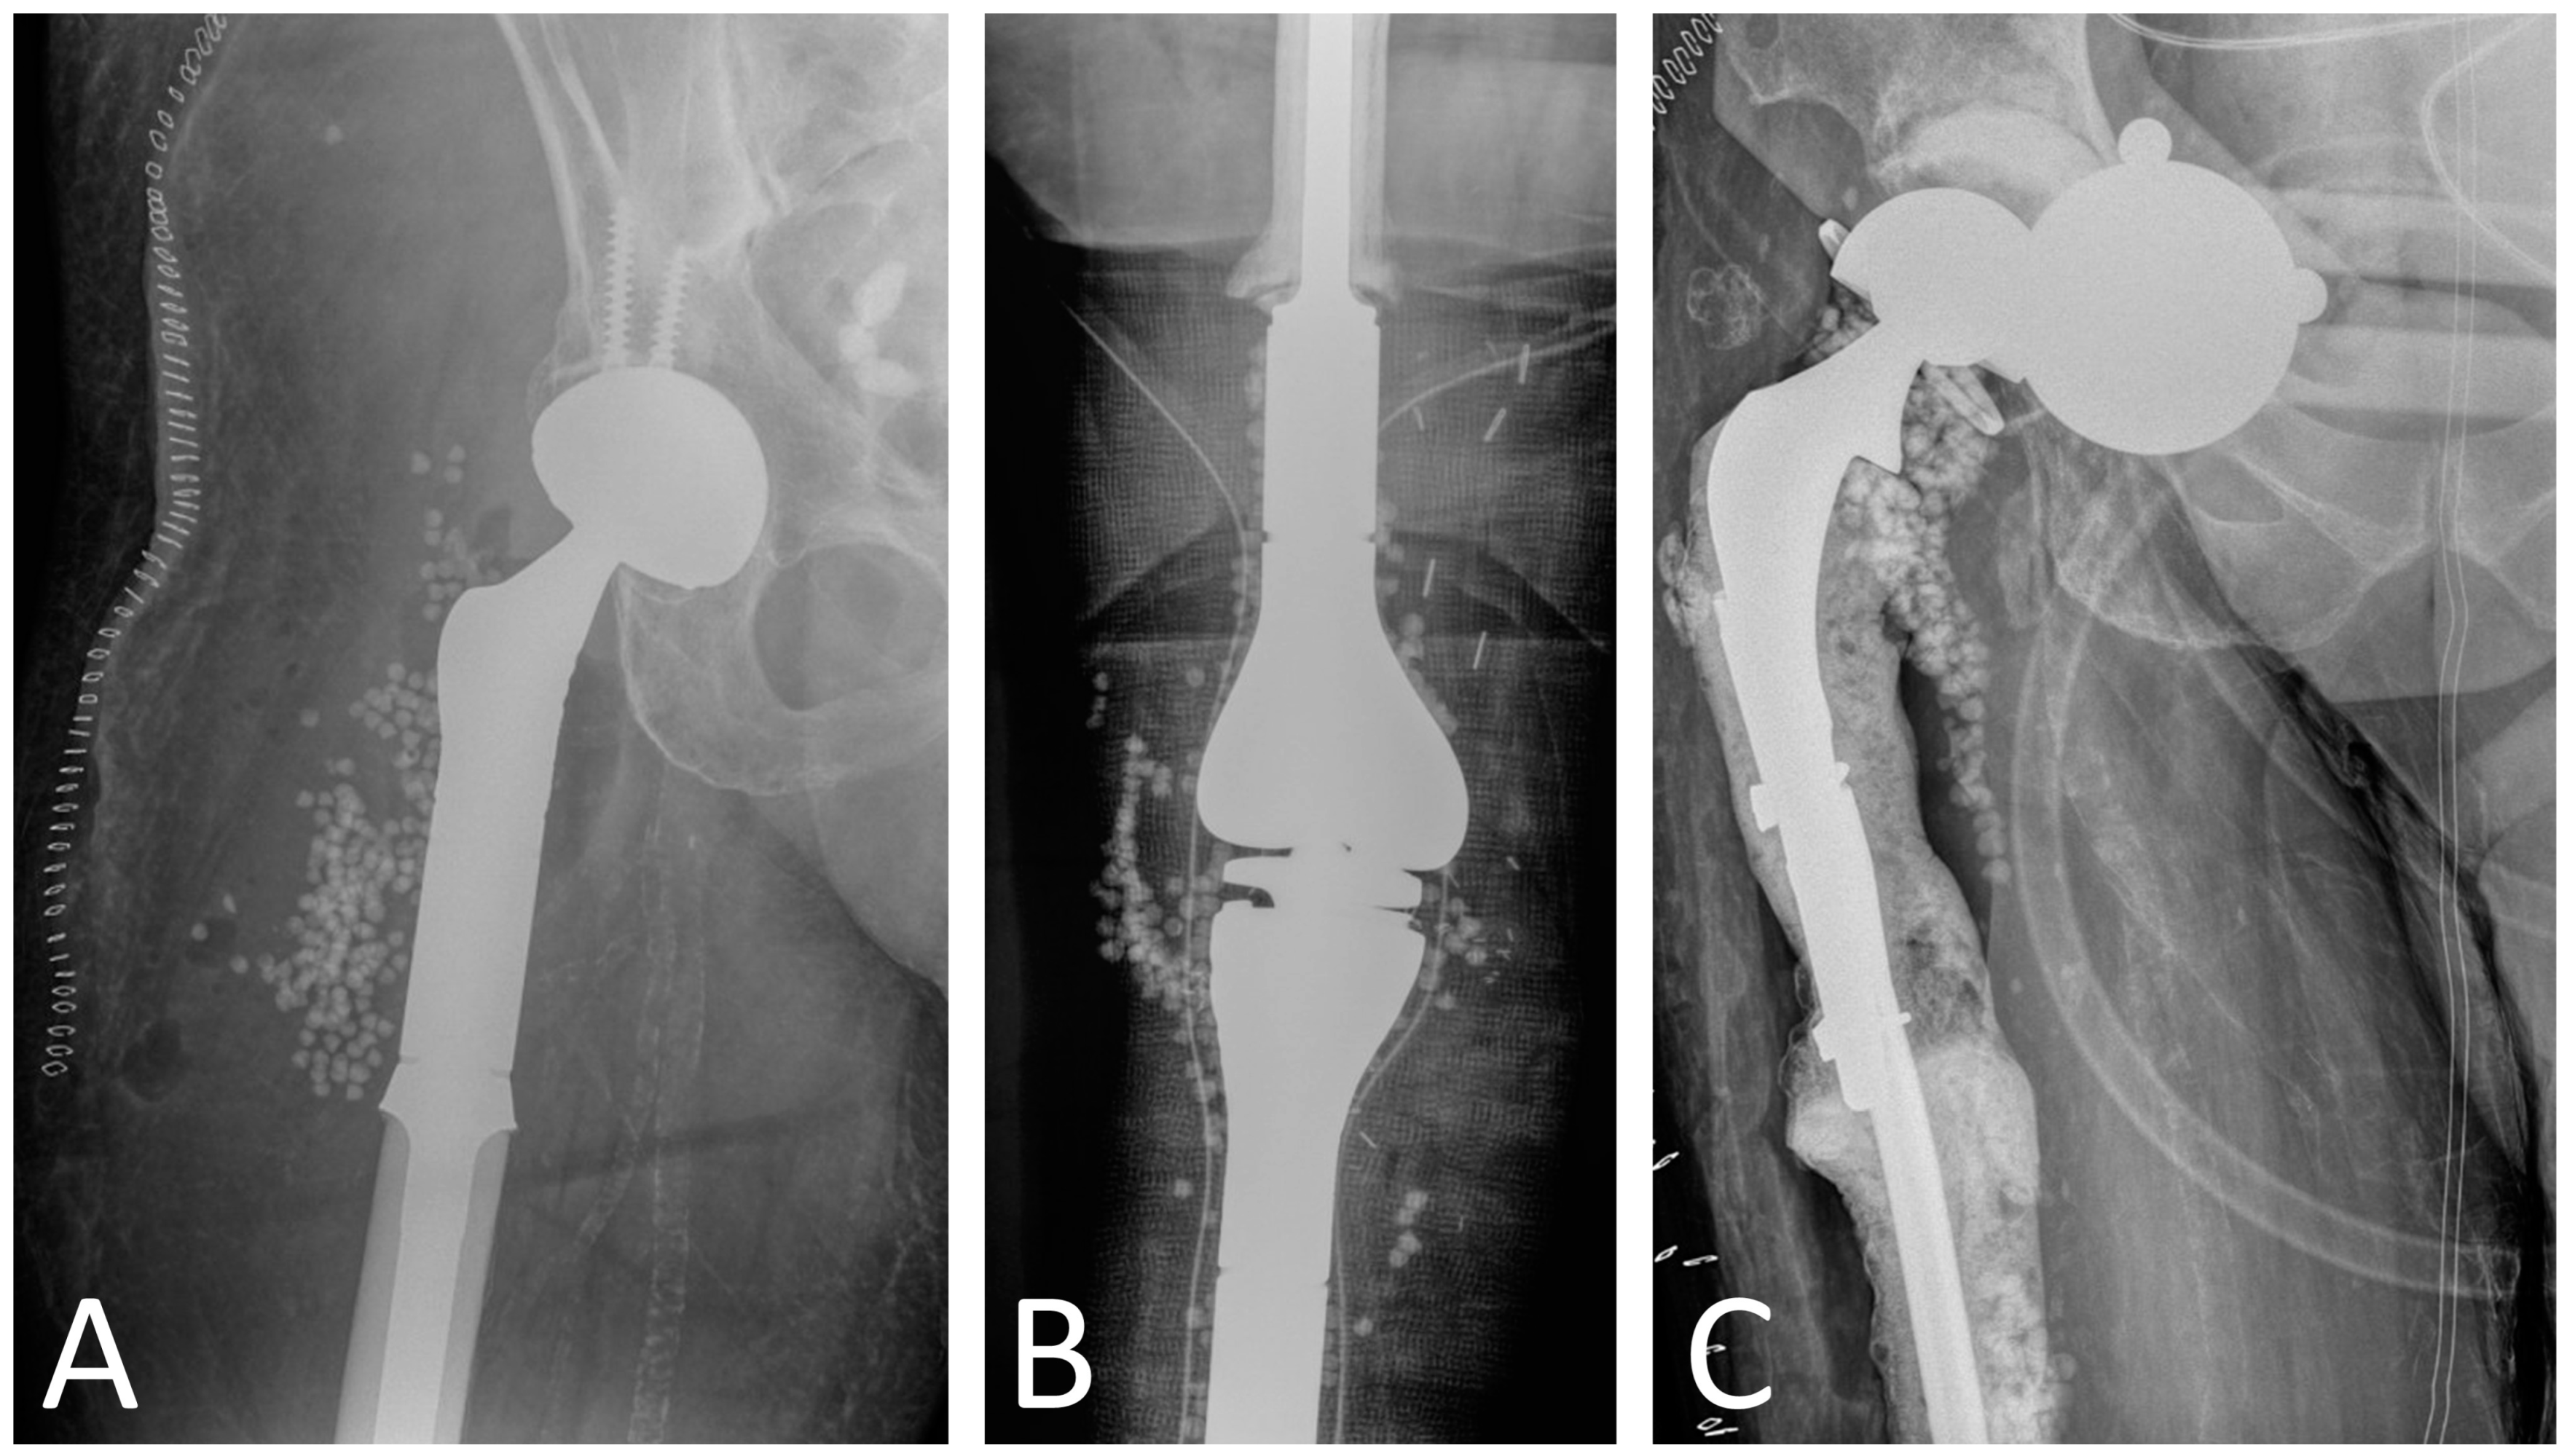

Two-stage revision is the gold standard for the management of megaprostheses PJI. This surgical strategy requires removal of all components, thorough soft tissue debridement, and placement of a cement spacer. Due to the morbidity of removing fixed components, some surgeons have advocated for a partial two-stage revision with stem retention, citing positive outcomes [37]. However, these findings stem from a single study that included 11 patients treated with this procedure and 4 patients with complete two-stage revision. In our opinion, retention of the stems does not allow for complete PJI eradication, and more recent data underscore this point [22]. Sigmund et al. analyzed the outcomes of 32 patients treated with two-stage revision for megaprostheses PJI and reported a 77% success rate for patients treated with complete stem removal and 36% for those with incomplete stem removal [22]. Regarding spacer construction for PJI involving megaprostheses around the knee, we recommend the use of two tibial nails, which serve as a scaffold for the antibiotic-loaded cement (Figure 1). Alternative spacer manufacturing techniques using Kuntscher nails and cement guns have been described [18]. Unless contraindicated, combination of 3 g of vancomycin and 3.6 g of tobramycin per 40 g package of bone cement is recommended [72]. Given the large size of these defects and the impossibility to use all cement bags with antibiotics, we recommend that the antibiotic cement is used at the bone–spacer interface and, secondarily, in the periphery of the spacer. A key feature in two-stage revisions is to ensure that a spacer of sufficient size is used to preserve the cavity in which the new prosthesis will be reimplanted in the second stage [18]. As patients with megaprostheses PJI often require higher doses of local antibiotics than those used in conventional PJI, surgeons should also be aware of the high risk of post-operative acute kidney injury (AKI) [77]. Underlying chronic kidney disease, high baseline creatinine, low preoperative hemoglobin, and blood transfusion requirement have been identified as risk factors for AKI after spacer insertion [78]. Although no specific time to reimplantation has been established, Jeys et al. recommended leaving the spacer in place for a minimum of six weeks [36]. Moreover, they recommended performing reimplantation only if no organism grew after three weeks of culture of periprosthetic aspirate. An antibiotic-free interval before joint aspiration (antibiotic holiday) of 2 weeks should be considered to minimize the number of false negative results [79].

Figure 1.

Radiographs of patient with distal femur replacement PJI treated with two-stage revision. (A) Pre-explantation radiographs, (B) intraoperative radiographs of the spacer with two tibial nails, and (C) post-reimplantation radiographs.